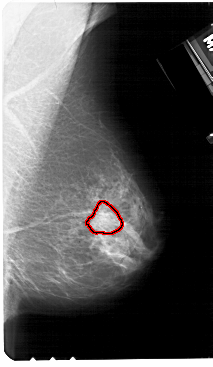

A_1533_1.LEFT_CC

LEFT_CC LINES 5041 PIXELS_PER_LINE 2971 BITS_PER_PIXEL 12 RESOLUTION 43.5 NON_OVERLAY

FILE: A_1533_1.RIGHT_CC.OVERLAY

TOTAL_ABNORMALITIES 1

ABNORMALITY 1

LESION_TYPE MASS SHAPE IRREGULAR MARGINS ILL_DEFINED

ASSESSMENT 4

SUBTLETY 3

PATHOLOGY MALIGNANT

TOTAL_OUTLINES 1

BOUNDARY